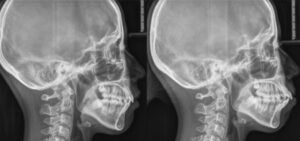

では,上の矯正治療前後のセファロ=頭部エックス線規格写真レントゲンの比較をご覧ください.

矯正歯科医によるバイマックスの治療前後

(バイマックス=両歯槽前突で口元のとんがった患者さんの矯正歯科医による矯正治療前後の口元の変化をセファロレントゲンの重ね合わせで評価 : 黒が治療前/赤が矯正治療後)

向かって右の矯正治療前のレントゲンでは頬張ったように突出していた口元が,矯正治療後では,きりっと引き締まって,美しいE-Line を描くようになったことがわかります.

しかし,この症例、非抜歯で矯正治療したところで、矯正治療したことにはなりません.価値ある治療結果が担保されないばかりか、機能性・安定性にも問題が残り、審美性についてはさらに大きな問題が残るでしょう.内外の学会における認定についても得られることはなく、判定は再治療.上の画像に見るような,プロの矯正歯科医が成し遂げた結果は得られない.つまり価値のある矯正治療は期待できません.

初診時,最近若い人たちがいうところの”口ゴボ”=突出していた口元はさらに前突し,口はもっと閉じにくくなり,オトガイの梅干しみたいな緊張はさらに強くなって,口も顔も大きくなってしまうでしょう.